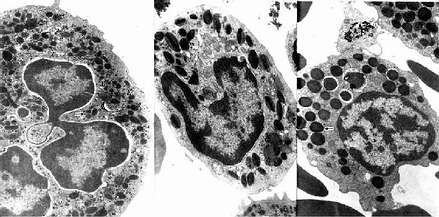

中性粒细胞的胞质染成粉红色,含有许多细小的淡紫色及淡红色颗粒,颗粒可分为嗜天青颗粒和特殊颗粒两种。嗜天青颗粒较少,呈紫色,约占颗粒总数的20%,光镜下着色略深,体积较大;电镜下呈圆形或椭圆形,直径0.6~0.7μm,电子密度较高(图5-4,5-5),它是一种溶酶体,含有酸性磷酸酶和过氧化物酶等,能消化分解吞噬的异物。特殊颗粒数量多,淡红色,约占颗粒总数的80%,颗粒较小,直径0.3~0.4μm,呈哑铃形或椭圆形,内含碱性磷酸酶、吞噬素、溶菌酶等。吞噬素具有杀菌作用,溶菌酶能溶解细菌表面的糖蛋白。

2.嗜酸性粒细胞 嗜酸性粒细胞(eosinophilic granulocyte,eosinophil)占白细胞总数的0.5%-3%。细胞呈球形,直径10~15μm,核常为2叶,胞质内充满粗大(直径0.5~1.0μm)、均匀、略带折光性的嗜酸性颗粒,染成桔红色(图5-2)。电镜下,颗粒多呈椭圆形,有膜包被,内含颗粒状基质和方形或长方形晶体(图5-4,5-5)。颗粒含有酸性磷酸酶、芳基硫酸酯酶、过氧化物酶和组胺酶等,因此它也是一种溶酶体。

3.嗜碱性粒细胞 嗜碱性粒细胞(basoophilic granulocyte,basophil)数量最少,占白细胞总数的0~15。细胞呈球形,直径10-12μm。胞核分叶或呈S形或不规则形,着色较浅。胞质内含有嗜碱性颗粒,大小不等,分布不均,染成蓝紫色,可覆盖在核上(图5-2)。颗粒具有异染性,甲苯胺蓝染色呈紫红色。电镜下,嗜碱性颗粒内充满细小微粒,呈均匀状或螺纹状分布(图5-4,5-5)。颗粒内含有肝素和组胺,可被快速释放;而白三烯则存在于细胞基质内,它的释放较前者缓慢。肝素具有抗凝血作用,,组胺和白三烯参与过敏反应。嗜碱性粒细胞在组织中可存活12-15天。

图5-5 人三种粒电镜像 ×17800

左图:中性粒细胞(白求恩医科大学尹昕、朱秀雄教授供图)

中图:嗜酸性粒细胞 左图:嗜碱性粒细胞

↑特殊颗粒,(

)嗜天青颗粒